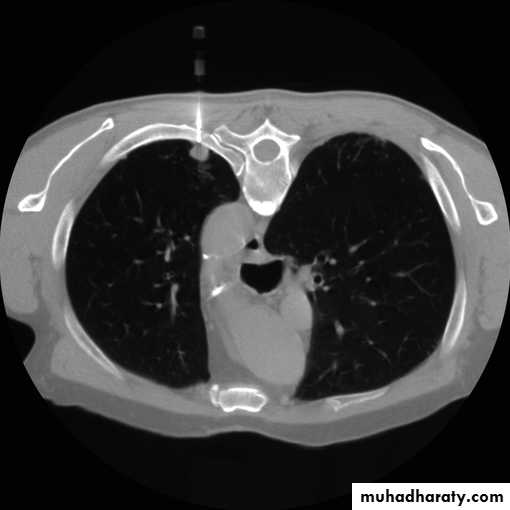

2-CT scan: indications:

• Assessment of trauma and emergency conditions.• assessment of masses( primary & secondary).

• Diagnosis Of interstitial disease.(HRCT...High resolution CT )

• guided procedures.

• CT angiography in suspected pulmonary embolism.

mediastinal window bone window lung window